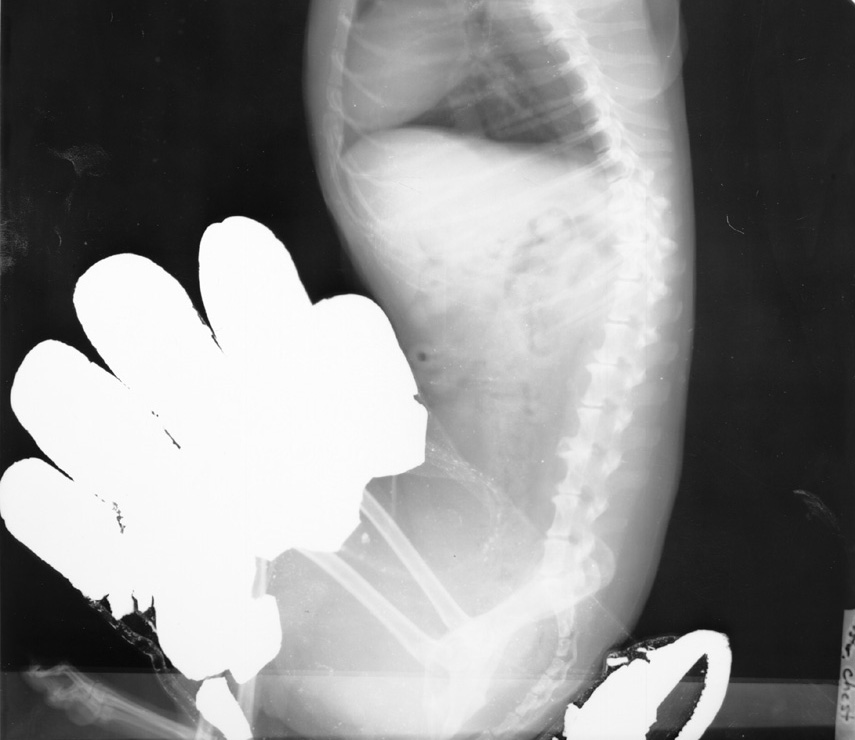

Hands in Primary Beam